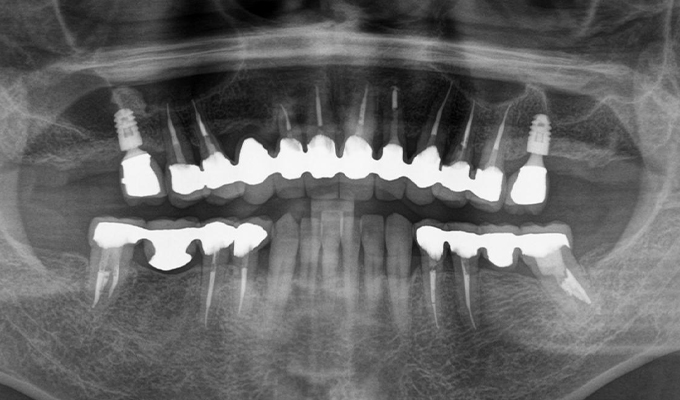

case1インプラントとメタルボンドブリッジの症例

初診時(2010年)

初回メンテナンス時(2014年)

- 初診時の年齢

- 60代女性(2010年)

- 主訴

- ちゃんと咬めるようになりたい。最近孫が生まれたから一緒に歌ったりしたいけど、今は歌うこともできないから・・・・。と

- 治療内容

- 5年ほど前に入れ歯を作ったそうですが合わなかったので使用してなかったせいか前歯がグラグラになっていて今にも抜けそうな状態でした。

保存が難しい歯を抜歯し、上はインプラント8本、下は奥歯にインプラント4本埋入しました。

補綴は変色しないメタルボンドを選択されたので治療完了して11年経過してもとてもきれいな状態で維持されています。

初診時にお話しされていたお孫さんも中学2年生になったそうで、歯の治療をしたおかげで充実した毎日が送れてます、とメンテナンス時もいつも嬉しそうにされています。